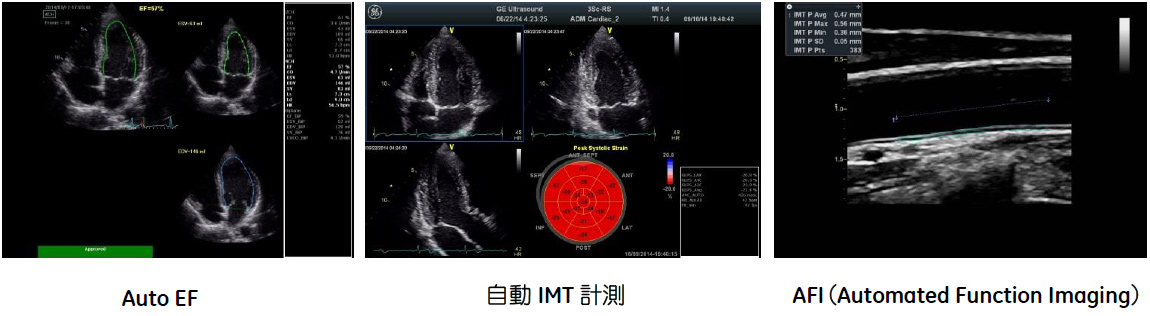

買い保障できる GEヘルスケア・ジャパン、循環器領域の開業医向けに最適な心 タイムセール